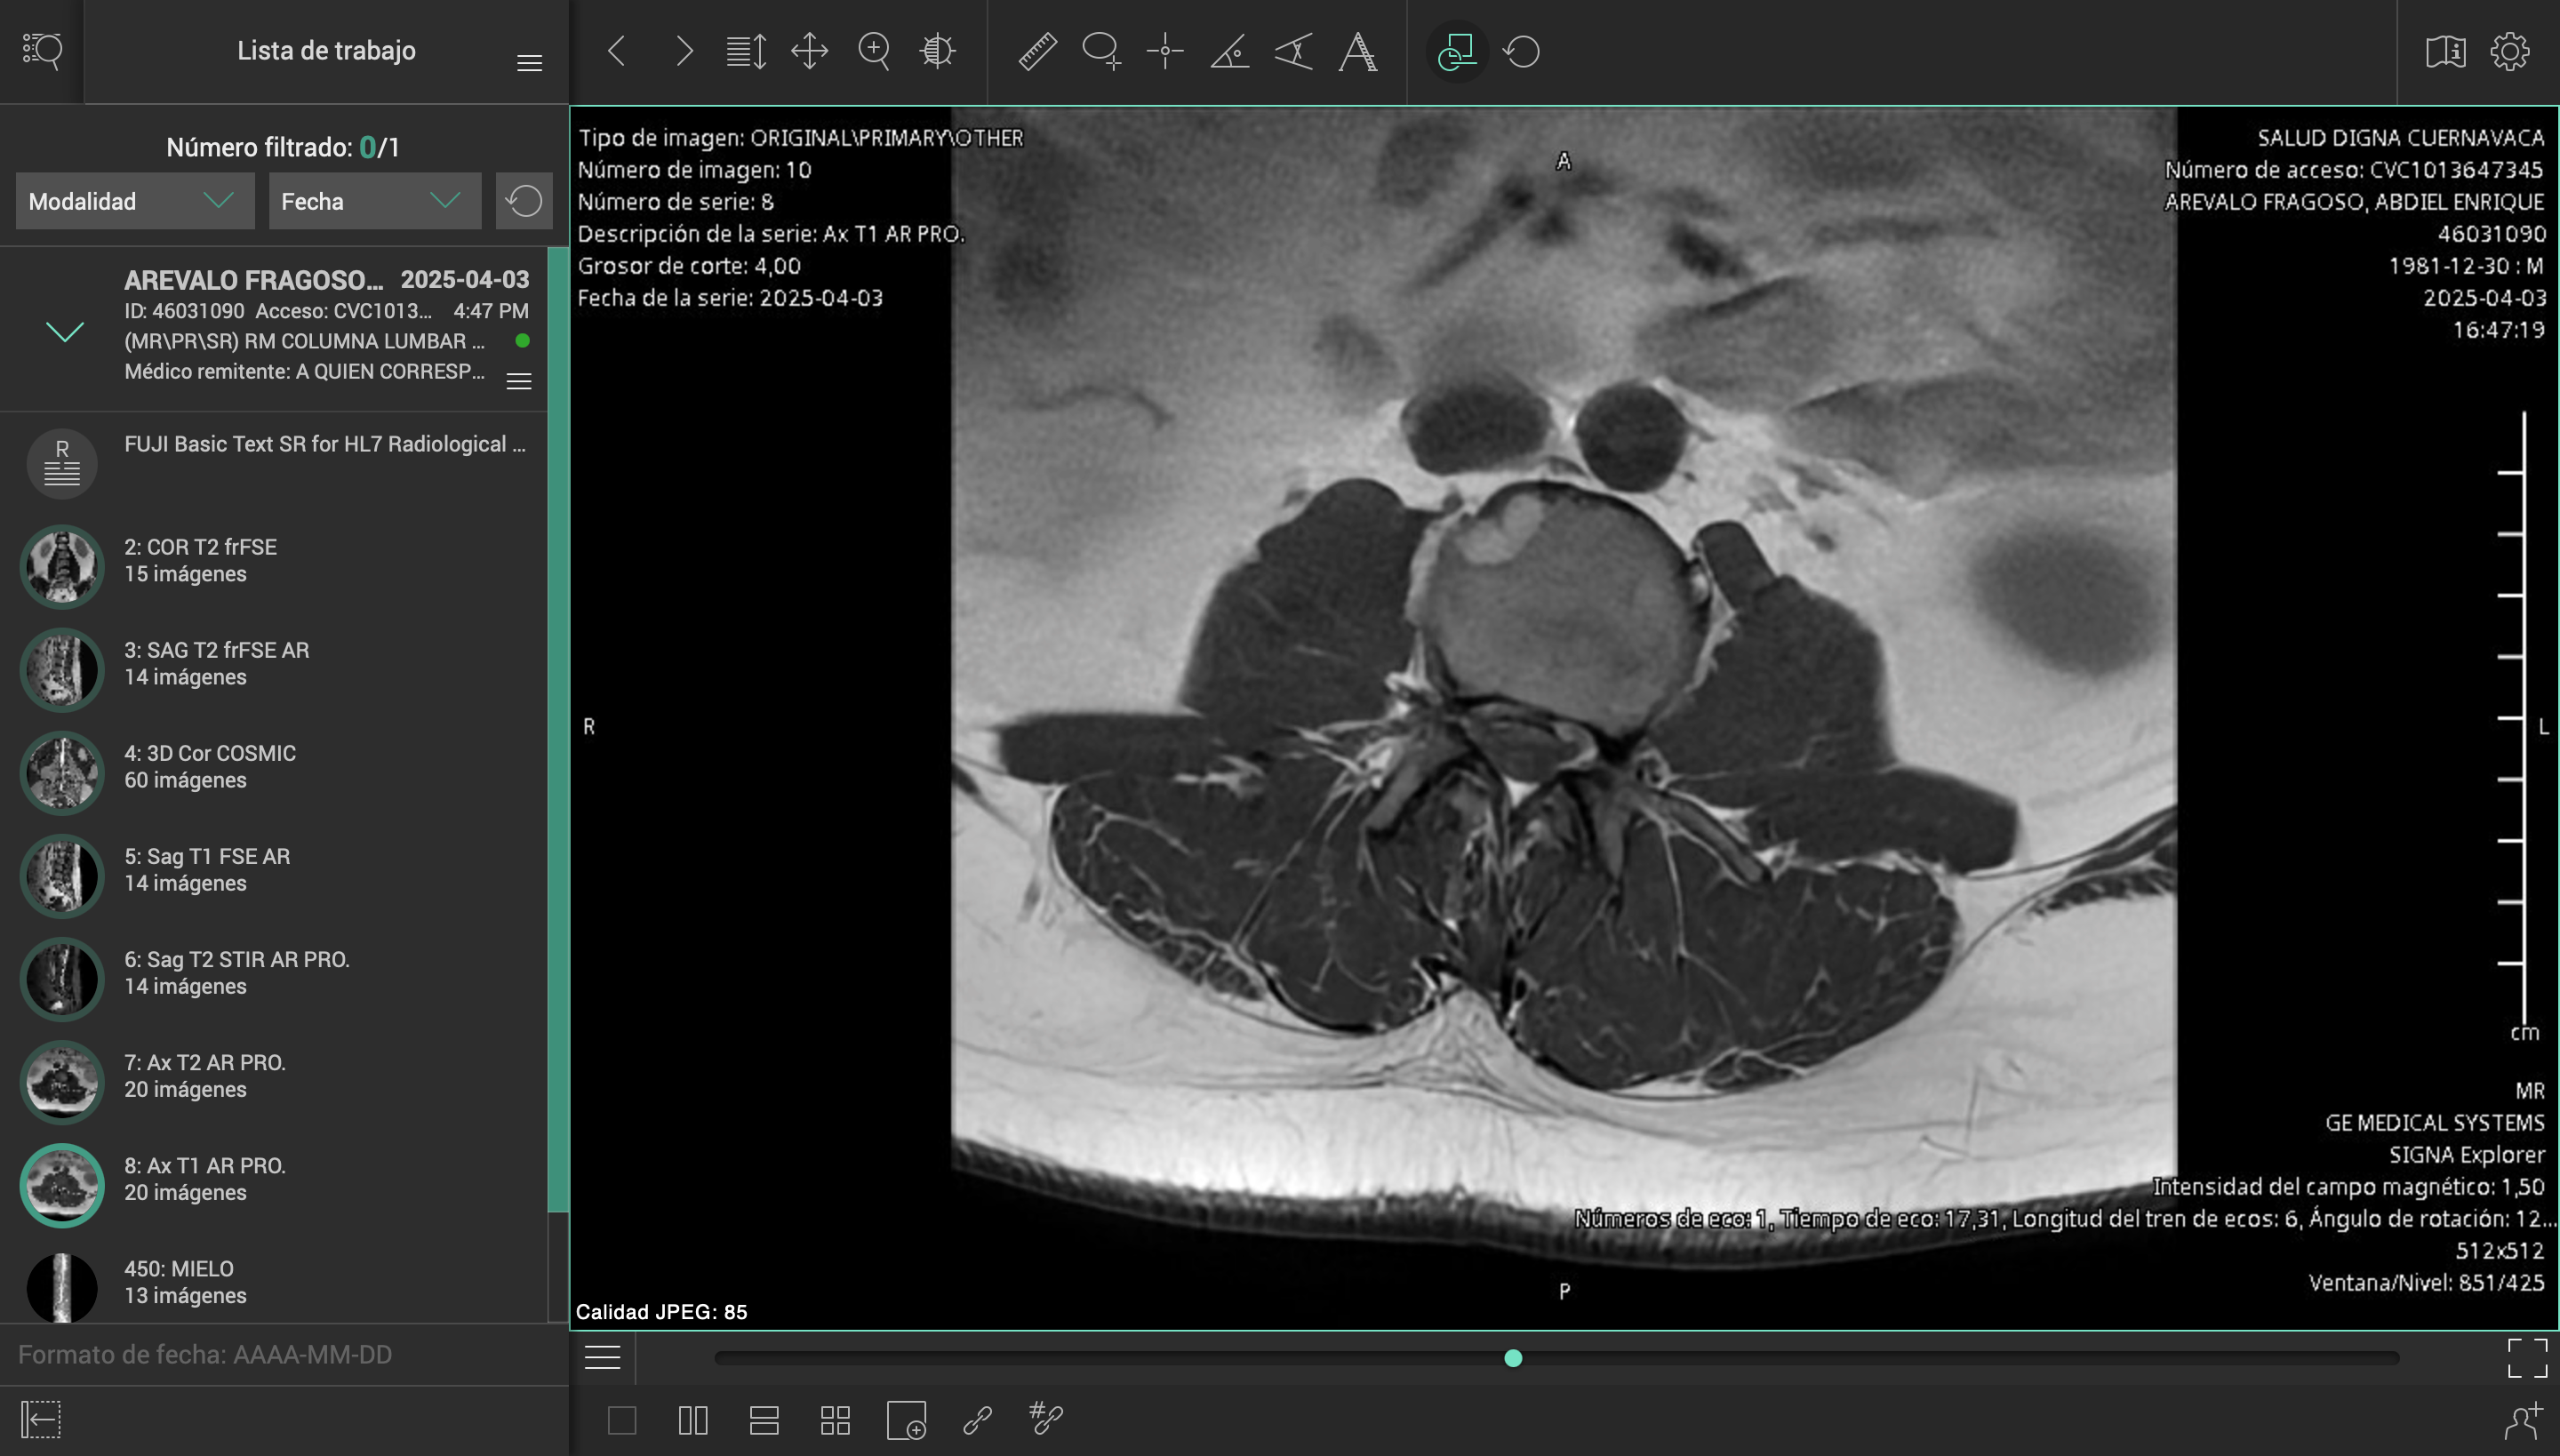

El pasado 2 de marzo de 2025, sufrí un accidente en carretera mientras conducía mi motocicleta. Un automóvil me impactó y me arrojó contra el asfalto, causándome lesiones severas en el hombro izquierdo, columna cervical y lumbar. El conductor se dio a la fuga, y hasta ahora no ha sido posible obtener justicia ni apoyo institucional.

Desde entonces, han pasado más de tres meses esperando una consulta con un especialista del ISSSTE, sin éxito. Durante este tiempo, mi salud ha empeorado, con complicaciones cada vez mayores por la falta de atención médica oportuna.

Esta situación me ha colocado en una condición muy vulnerable, médica, emocional y económicamente. Los tratamientos, terapias y cirugías necesarias superan los casi un millón de pesos mexicanos, una cifra que me resulta imposible cubrir por mi cuenta.

Es por ello que me veo en la necesidad de iniciar este fondeo, para poder comenzar al menos con la primera parte del tratamiento, y frenar el avance de las lesiones, mientras buscamos cómo costear el resto de la atención médica que necesito para recuperar mi salud y movilidad.